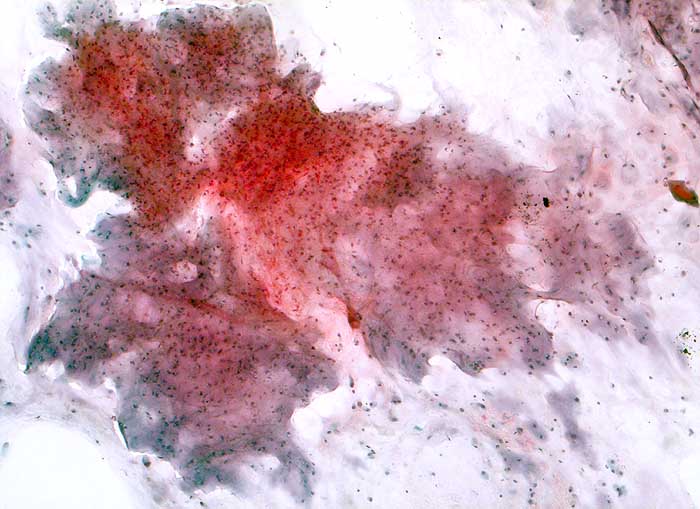

Die Zytologie des Chondrosarkoms ist charakterisiert durch neoplastische Chondrozyten auf einem Hintergrund von chondroider Matrix. Maligne Chondrozyten sind oval oder polygonal. Die Zellen sind locker kohäsiv oder liegen einzeln. Die Tumorzellen sind gelegentlich in Lakunen der hyalinen Matrix eingeschlossen. Vakuolisiertes oder granuläres Zytoplasma ist reichlich vorhanden. Die Kerne sind uniform, rund bis oval und können prominente Nukleolen enthalten. Zellreichtum, Kernatypien, Mehrkernigkeit und Mitosefiguren nehmen zu mit zunehmendem Tumorgrad. Bei den hochmalignen Chondrosarkomen enthalten die zellreichen Ausstriche fast ausschliesslich myxoide Matrix, die sich in der PAP Färbung schwach, in der MGG Färbung deutlich anfärbt.

Die verschiedenen Subtypten des Chondrosarkoms sind zytologisch wegen fliessender Übergänge nicht sicher zu unterscheiden. Die Kombination hohes Patientenalter, radiologische Zeichen eines destruktiven Wachstums, hohe Zellularität und Kernpolymorphie lassen bei knorpelbildenden Tumoren auf Malignität schliessen.